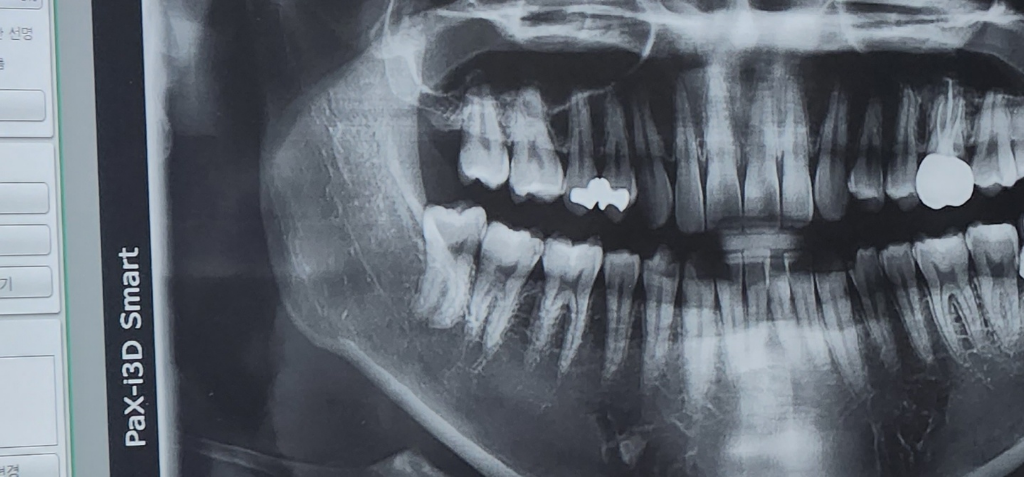

사랑니 너무 무서워요 충치치료로 가능한가요?

아래쪽 사랑니를 빼긴 싫은데 (너무 아프고 무서워서)

살짝 검게 올라왔네요 이가 좀 썩은 거 같은데 뽑긴 너무 싫은데 치료도 가능할까요? 추가로 저 사랑니 뽑기 어려운 사랑니 인가요??

뿌리가 길어보이지만 똑바로 나와있기 때문에 발치가 어려운 케이스는 아닐것으로 생각됩니다.

크게 어려운 사랑니는 아닌거 같습니다. 다만 나이가 잇고 교합이 되는 사랑니라서 뽑을때 시간이 조금은 걸릴수도 잇을것같습니다. 잇몸을 열거나 뼈를 삭제하는 경우는 아니니 크게 걱정은 안하셔도 될것같습니다.

해당 사랑니는 뽑기 어려운 사랑니가 아니며 관리가 잘 되지 않는다면 미리 발치하는 것이 좋습니다. 사랑니는 결국에는 발치를 하기 때문에 치료해서 사용하지는 않습니다. 따라서 지금 상태에서는 사랑니 치료가 아닌 발치를 고려하는 것이 맞아 보입니다.